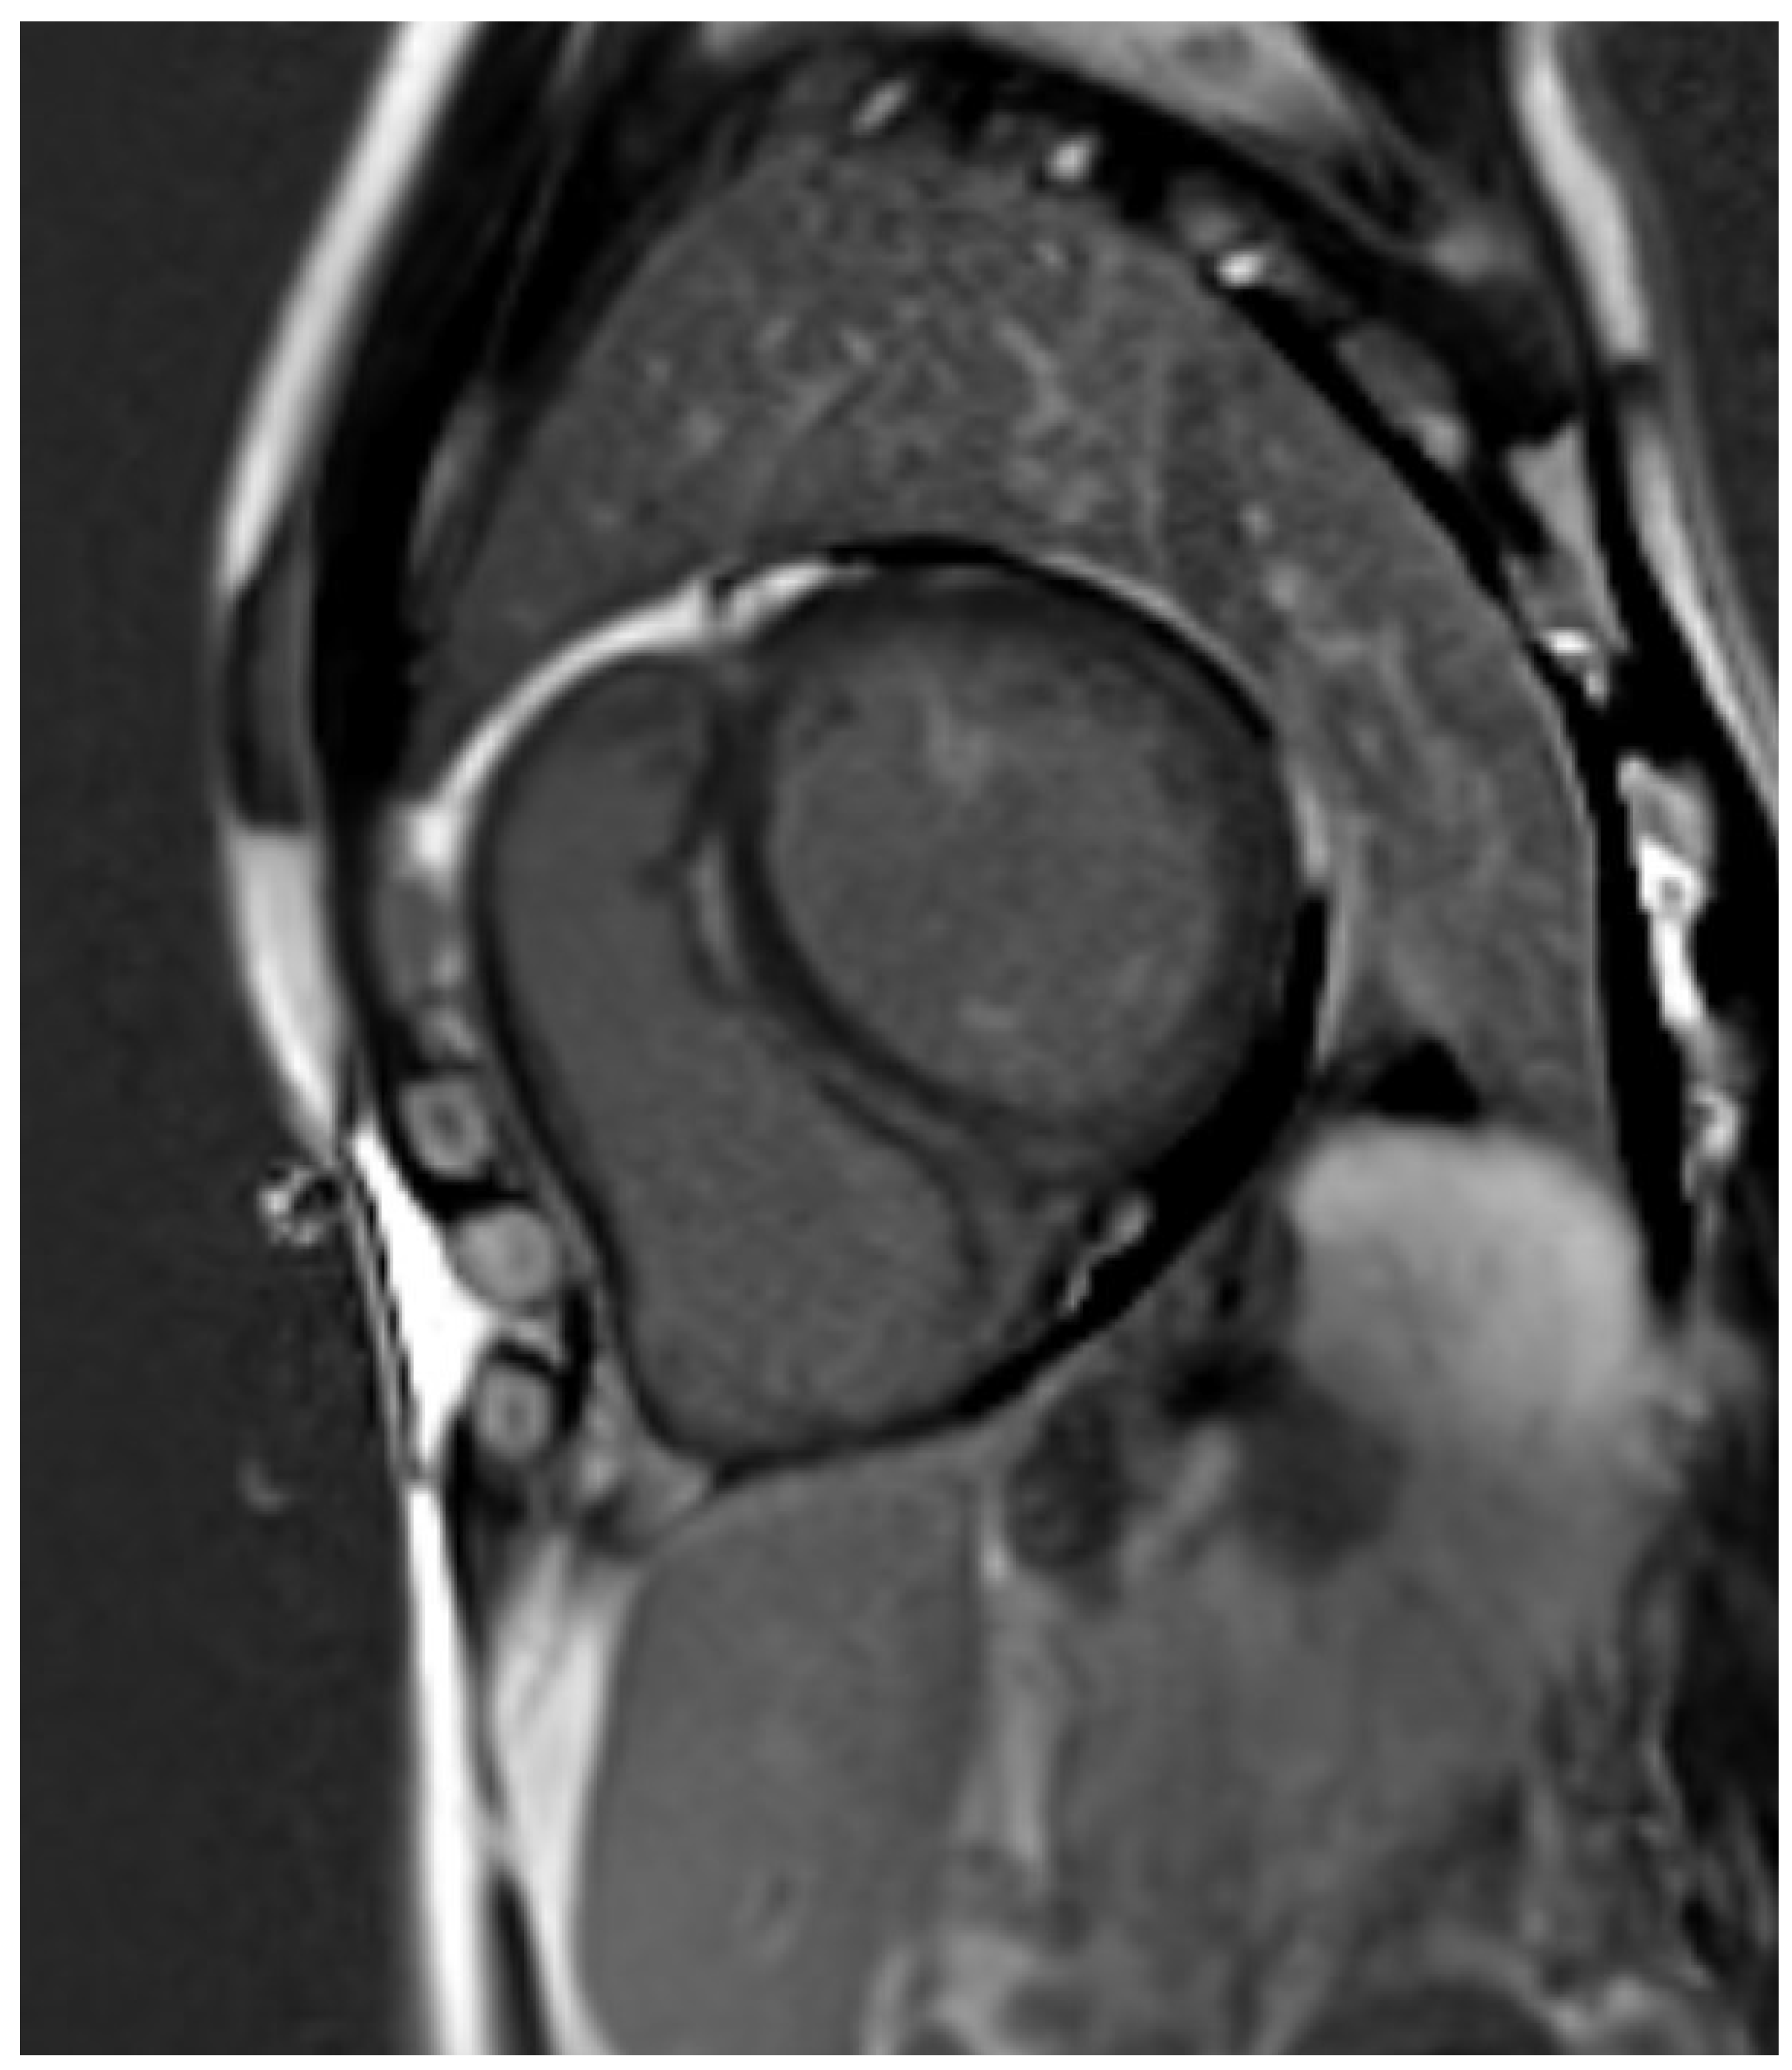

2.1. Assessment of Left and Right Ventricular Function